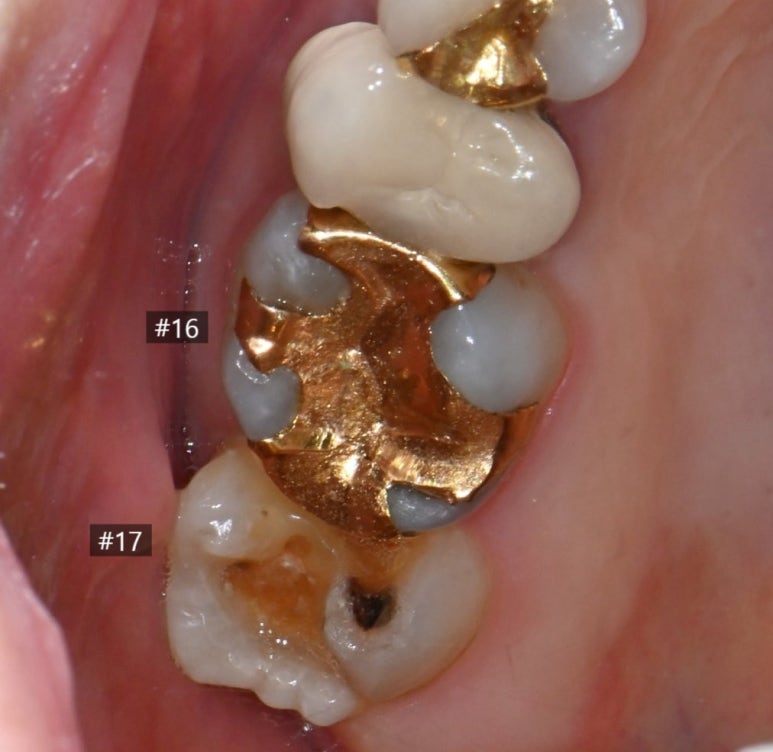

오른쪽 위 큰 어금니(#17)의

금 인레이가 빠진 상태로 내원하셨습니다.

금 인레이가 왜 떨어졌는지 확인해보니

안타깝게도 인레이 하방으로 2차 충치가 진행되어 있었고,

그 영향으로 치아 일부분도 깨져나간(파절) 상태였습니다.

다행히 파절 범위가 아주 넓지는 않아

전체를 씌우는 크라운 대신,

치아 삭제를 최소화하는 세라믹 수복이 가능한 상황이었습니다.

25.11.11 #17 치아의 금 인레이가 탈락하고 충치가 발생한 모습.

25.11.11 앞쪽 어금니(#16) 금 인레이 하방에서 발견된 충치